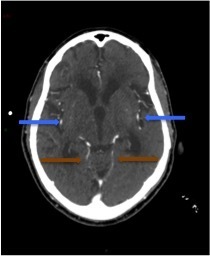

Un scanner cérébral sans injection est réalisé. Les reformations axiales vous sont présentées.

Question 10 : Ce scanner présente :

Les espaces sous sous-arachnoidiens ne sont plus visibles. Ne pas confondre la substance grise qui arrive au contact des os du crâne, avec une hyperdensité spontanée méningée.

Le volume des ventricules paraît faussement augmenté du fait de l’effacement diffus des sillons corticaux.

Qui traduit une augmentation du volume cérébral.

Aucun des deux hémisphères cérébraux ne passe sous la faux du cerveau. L’augmentation du volume cérébral est diffuse.

Effacement diffus des sillons corticaux avec début de dédifférenciation des de la substance blanche - substance grise notamment des noyaux centraux. Cela traduit un œdème cérébral diffus secondaire à un bas débit cérébral.

Question 13 : Cet angioscanner présente :

Le diagnostic de mort encéphalique en angioscanner, selon les recommandations de la Société Française de Neuroradiologie, repose sur :

l’absence d’opacification des veines profondes (veines cérébrales internes (Figure 24 flèches marrons) et grande veine cérébrale (Figure 25 flèche jaune)

l’absence d’opacification bilatérale des branches corticales des artères cérébrales moyennes (Figure 24 flèches bleues). (En complément, sur la Figure 25, flèche orange : les artères péricalleuses qui sont des branches issues des artères cérébrales antérieures).